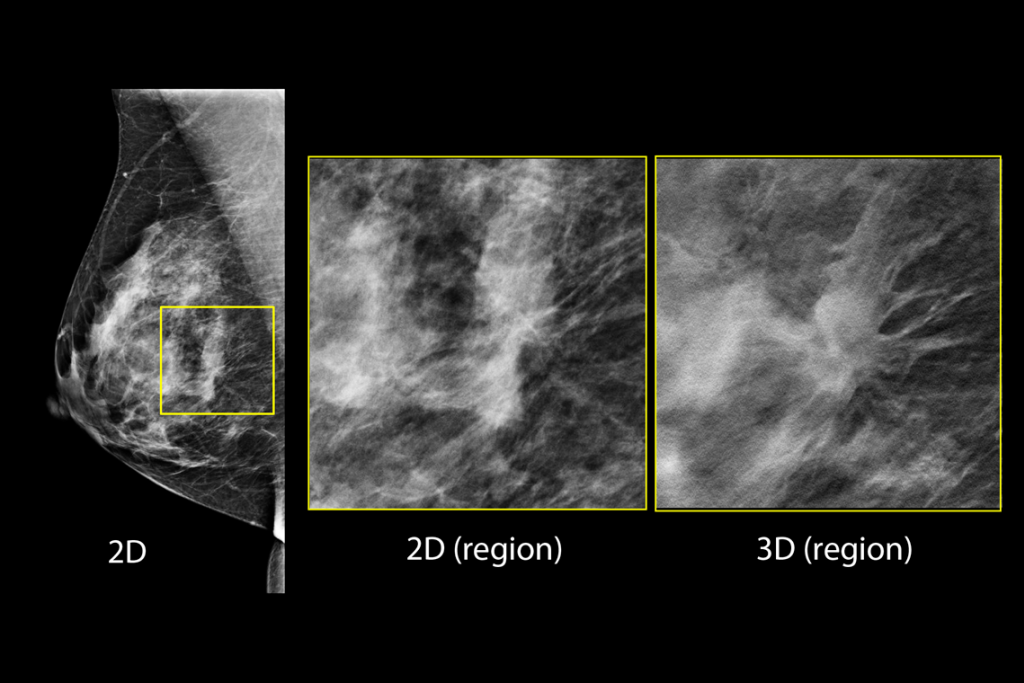

Clinical Images

Clinical images of breast scan mammography

Clinical images of breast scan with suspicious Lesion

Clinical images of breast scan